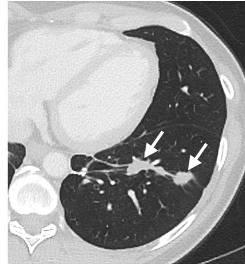

Lung CT scan taken six months after ACT with mutation-specific T-cells, showing shrinkage of metastatic tumors in the lung tissue, with arrows pointing to the reduced tumor sites.

Six months after ACT with mutation-specific T-cells, tumors that metastasized to the lung have shrunk.

Following transfer of the TILs, the patient's metastatic lung and liver tumors stabilized. When the patient's disease eventually progressed, after about 13 months, she was re-treated with ACT in which 95 percent of the transferred cells were mutation-reactive T cells, and she experienced tumor regression that was ongoing as of the last follow up (six months after the second T-cell infusion). These results provide evidence that a T-cell response against a mutant protein can be harnessed to mediate regression of a metastatic epithelial cell cancer.